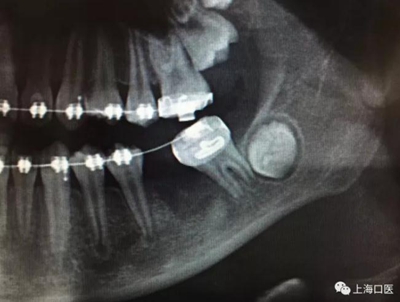

這是上海武廣增正畸工作室接診的一例非常規(guī)拔牙矯治病例,患者女性,初診年齡14歲。LL6殘冠拔除。LL7近中平移取代LL6,我們上傳了該患者一組下頜磨牙近中平移連續(xù)矯治過程的正畸X線片,與正畸界朋友分享。

來源:武廣增 上??卺t(yī)